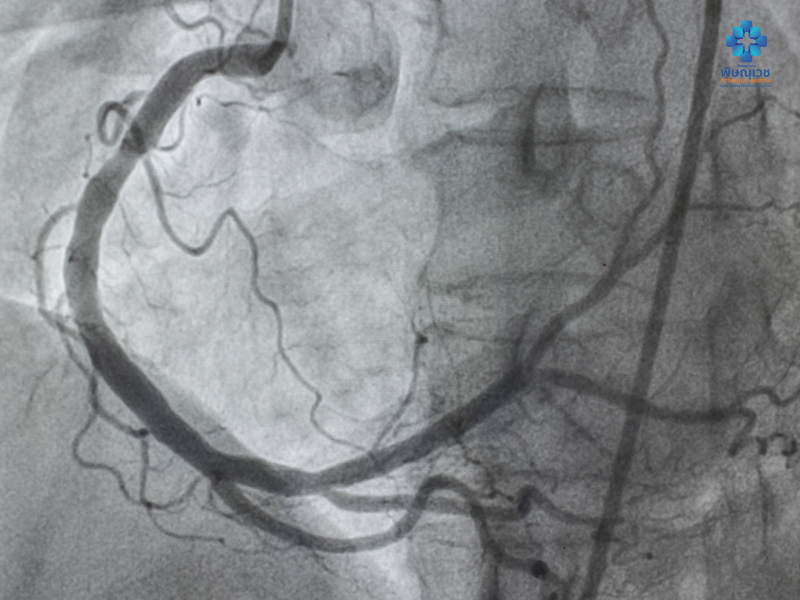

การฉีดสีหลอดเลือดหัวใจ (Coronary Angiogram หรือ CAG)

การฉีดสีหลอดเลือดหัวใจ (Coronary Angiogram หรือ CAG)

บางทีเรียก “การฉีดสี” เป็นการสอดสายสวนผ่านหลอดเลือดแดงแล้วฉีดสารทึบรังสีเพื่อตรวจวินิจฉัยการอุดตันและการตีบตันของหลอดเลือดหัวใจ หากพบความผิดปกติสามารถทำการรักษาต่อด้วยการทำบอลลูนและใส่ขดลวด

เป็นการรักษาโรคหลอดเลือดหัวใจตีบที่ง่ายและสะดวกเพราะไม่ต้องผ่าตัด เมื่อแพทย์วินิจฉัยจากการฉีดสีพบมีภาวะหลอดเลือดหัวใจตีบแคบ แพทย์จะรักษาโดยการสอดสายเข้าไปยังหลอดเลือดหัวใจบริเวณที่ตีบแคบหรือตัน แล้วขยายด้วยบอลลูน หรือใส่ "ขดลวด" (Stent) เพื่อให้หลอดเลือดขยายจนเลือดสามารถไปเลี้ยงกล้ามเนื้อหัวใจได้อีกครั้ง